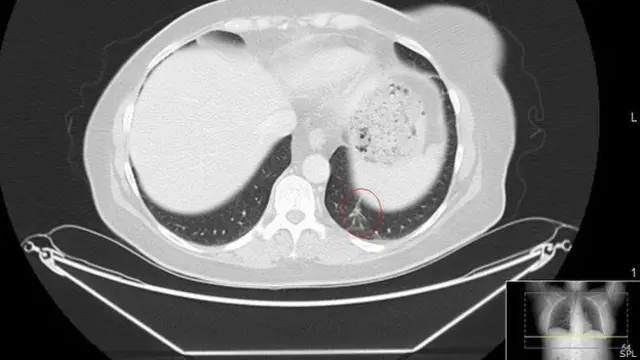

Новообразование на ее лице, которое считалось доброкачественным, оказалось на самом деле меланомой и дало метастазы в легкие. Врачи давали ей 18-24 месяца жизни.

Кейт прошла курс лечение в больнице Марсден и ее опухоль прекратила рост, однако она была вынуждена выйти из программы испытаний из-за побочных симптомов.